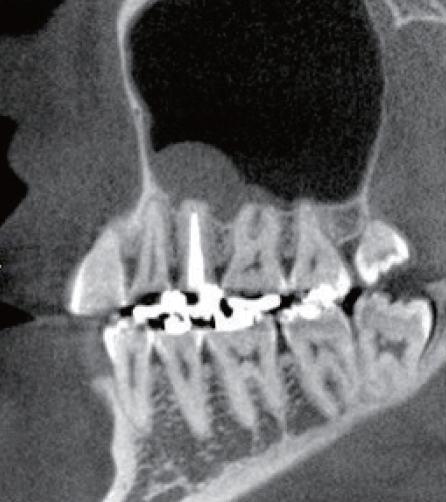

初診時のデンタルX線像を示す。レントゲン所見では根尖周囲組織に炎症を示す像を認め、その影響が上顎洞粘膜の肥厚の原因と推測されるレントゲン像である。

左上5番を他院で根管充填後、打診痛が消失しないので転院され受診患歯にはインレー修復がされている。根尖部は上顎洞と近接しており、上顎洞粘膜の肥厚も認められた

(症例1・①)根管充填の状態は比較的良好である。根管拡大・形成の3次元的評価のためCBCTを撮影。

CT像左上5番根尖部を中心として上顎洞粘膜の肥厚が認められ、根尖性歯周組織炎の影響が上顎洞まで及んでいると考えられた

根管処置後の修復が保存修復されて髄室開拡に制限があり、歯頸部周辺に存在する頬口蓋側に広がる髄角の形態が確認でき(症例1・②)、この部分に根管拡大不足の可能性を疑えた。根尖病変の原因として、頬口蓋的な根管拡大不足による起炎物質の取り残しによる感染が要因の一つであると診断した。より的確な予防形成を行うにあたり、器具操作の向上のため髄室開拡の修正が必要であると判断した。よって最終修復は歯冠修復による補綴修復が必要であると患者に説明し、承諾が得られたので再治療を行なった。

(症例1・②)

線で示した部分に髄角部の形態がそのまま残存していることが予測され拡大不足、未処置部分が存在すると判断した